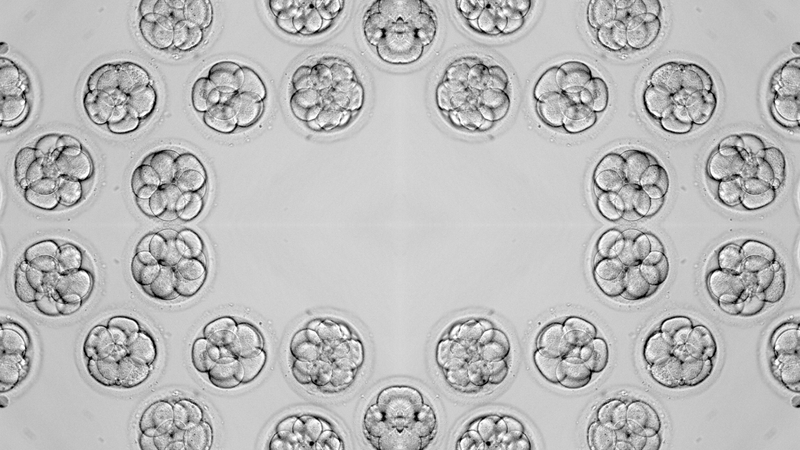

Vì sao phôi không bám vào tử cung sau chuyển phôi? Đây là câu hỏi thường gặp ở các cặp vợ chồng thực hiện thụ tinh trong ống nghiệm (IVF). Bài viết dưới đây sẽ làm rõ nguyên nhân và các giải pháp hỗ trợ giúp tăng khả năng làm tổ của phôi thai.

Vì sao phôi không bám vào tử cung là thắc mắc và cũng là nỗi lo lắng của rất nhiều cặp vợ chồng đang trong hành trình tìm kiếm con yêu, đặc biệt là những người thực hiện phương pháp thụ tinh trong ống nghiệm (IVF). Mặc dù IVF mang lại hy vọng cho các cặp vợ chồng hiếm muộn, nhưng tỷ lệ thành công phụ thuộc vào nhiều yếu tố, trong đó có khả năng làm tổ của phôi thai. Hiểu rõ nguyên nhân vì sao phôi không bám vào tử cung sẽ giúp các cặp vợ chồng có sự chuẩn bị tốt hơn và tăng cơ hội thành công trong quá trình điều trị.

Có nhiều yếu tố ảnh hưởng đến khả năng làm tổ của phôi thai. Nguyên nhân phôi không bám vào tử cung có thể xuất phát từ bản thân phôi thai, niêm mạc tử cung hoặc các yếu tố khác.

Chất lượng phôi đóng vai trò quan trọng trong việc làm tổ thành công. Phôi thai khỏe mạnh, có cấu trúc di truyền bình thường sẽ có khả năng bám dính và phát triển tốt hơn. Ngược lại, phôi thai kém chất lượng, mang gen di truyền bất thường hoặc bị tổn thương trong quá trình nuôi cấy, sẽ khó bám vào niêm mạc tử cung. Tuổi tác của người mẹ, chất lượng trứng và tinh trùng cũng ảnh hưởng đến chất lượng phôi thai.